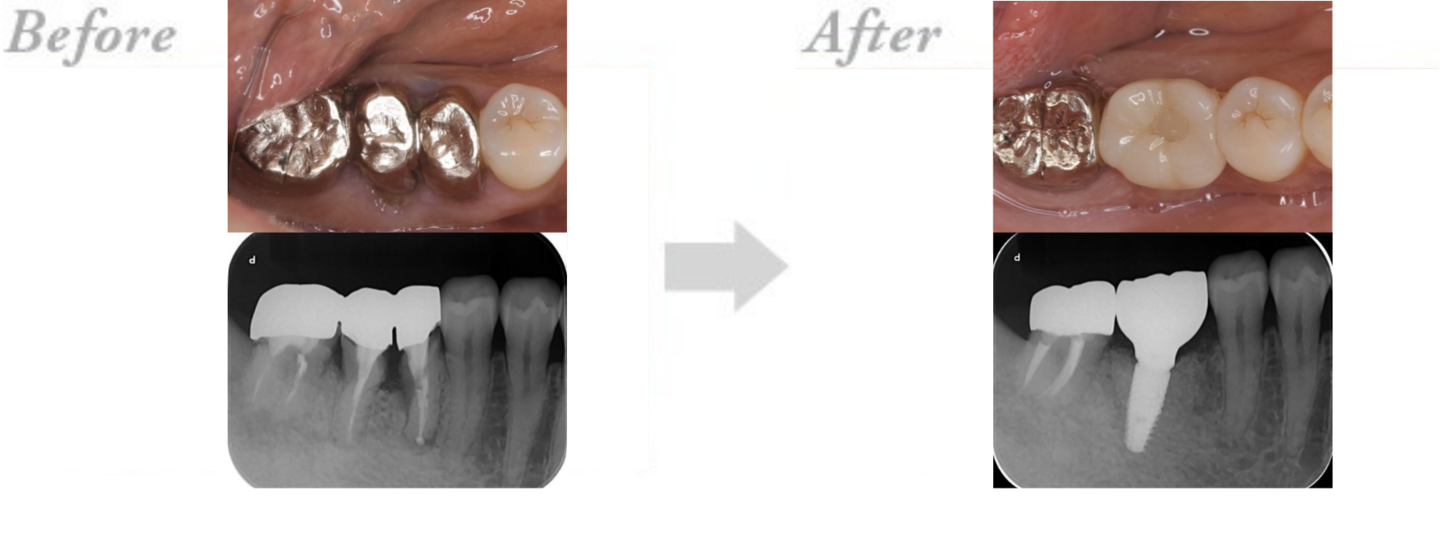

◆インプラント治療の実例 CASE2